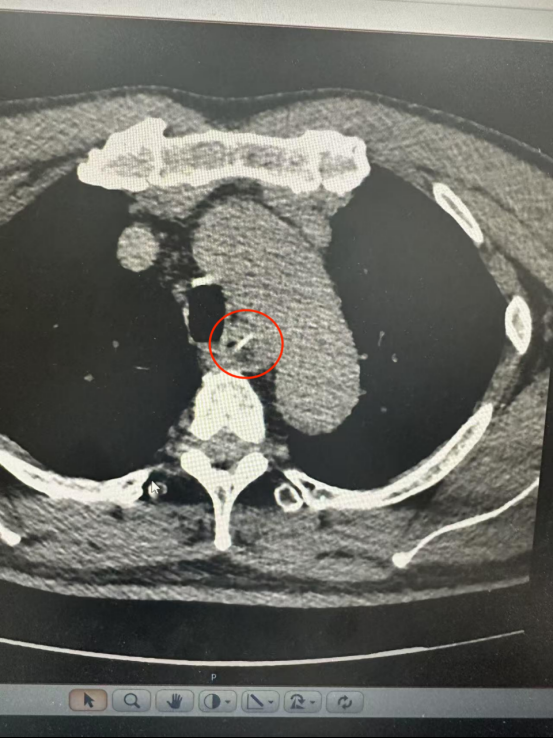

CT結(jié)果顯示一根長約25毫米的魚骨卡在食管中段,兩端分別緊貼食管管壁外緣與主動脈弓內(nèi)側(cè)。主動脈是人體最粗大的動脈血管,魚骨所處位置極為危險。

根據(jù)CT三維重建結(jié)果,魚骨緊貼主動脈弓但未刺破主動脈及食管全層,尖端與主動脈切線垂直,呈“一”字型排列。